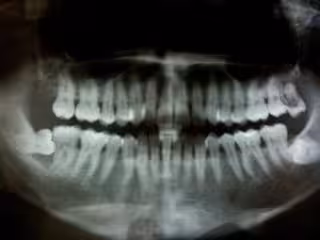

Más de 12 millones de españoles padecen periodontitis

Se trata de una enfermedad que tiene importantes consecuencias en la cavidad bucal, en la calidad de vida y en la salud general de los pacientes, siendo un importante problema de salud pública. En este sentido, la doctora Elena Figuero ha informado de que las principales enfermedades sistémicas relacionadas con la periodontitis son la diabetes, las patologías cardiovasculares o los efectos adversos durante el embarazo.